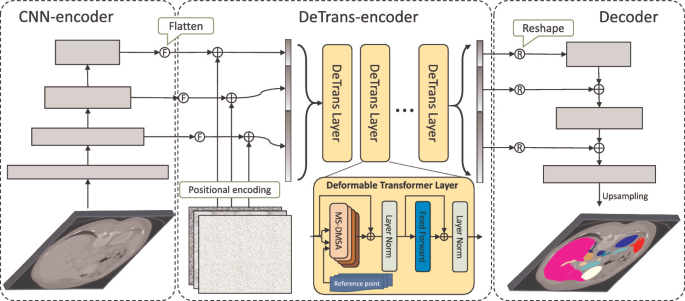

FAT-Net 属于最早期应用 Transformer 架构的经典医学图像图像分割网络,致力于解决皮肤病变分割任务。整个网络基于编解码架构,编码器部分采用 Transformer + CNN 的并行双分支架构进行主要的特征提取,以有效地捕获远程依赖关系和全局上下文信息。随后,基于特征重标定的策略对来自不同架构所提取到的的特征图进行更深层次的融合,通过学习的方式来自动获取到每个特征通道的重要程度,最后再筛选出更加有用的特征图。最后,通过在跳跃连接部分集成了特征自适应模块(FAM)来激活有效通道和抑制不相关的背景噪声,从而增强相邻层特征之间的特征融合。